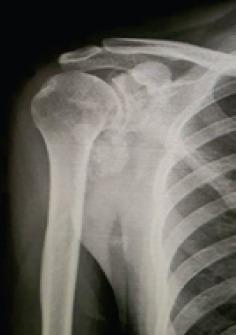

Here, we report a rare case of synovial chondromatosis affecting the right shoulder joint in a 23-year-old male with a 5-year disease duration who presented with progressive pain and restriction in movements which were impacting his routine activities. The loose bodies were removed using the arthroscopic approach combined with a partial synovectomy, and intra-articular methylprednisolone post procedure. The patient showed an excellent recovery in joint mobility within 4 weeks post-operatively, and there were no clinical signs of recurrence during a 6-month follow-up period.

在此,我们报告一例罕见的滑膜软骨瘤病病例,该病例发生在一名23岁男性的右肩关节,病程为5年,患者出现进行性疼痛和活动受限,影响其日常活动。采用关节镜手术联合部分滑膜切除术取出游离体,并在术后关节腔内注射甲基强的松龙。患者术后4周内关节活动度恢复良好,在6个月的随访期内无复发的临床迹象。